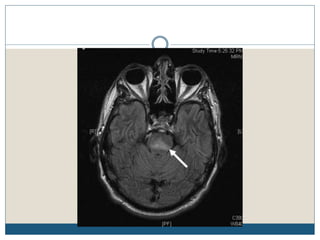

Typical MRI lesions

 Trident shaped / spreading bushfire pattern in central pons

 Signal characteristics of affected region include:

 T1: mildly or moderately hypointense

 T2: hyperintense, sparing the periphery and corticospinal tracts

 FLAIR: hyperintense

 DWI: hyperintense

 ADC: signal low or signal loss

 T1 C+ (Gd): usually there is no enhancement

 Radiologic findings do not improve over time, despite complete or nearly complete

clinical recovery

Typical MRI lesions Trident shaped / spreading bushfire pattern in central pons  Signal characteristics of affected region include:  T1: mildly or moderately hypointense  T2: hyperintense, sparing the periphery and corticospinal tracts  FLAIR: hyperintense  DWI: hyperintense  ADC: signal low or signal loss  T1 C+ (Gd): usually there is no enhancement  Radiologic findings do not improve over time, despite complete or nearly complete clinical recovery